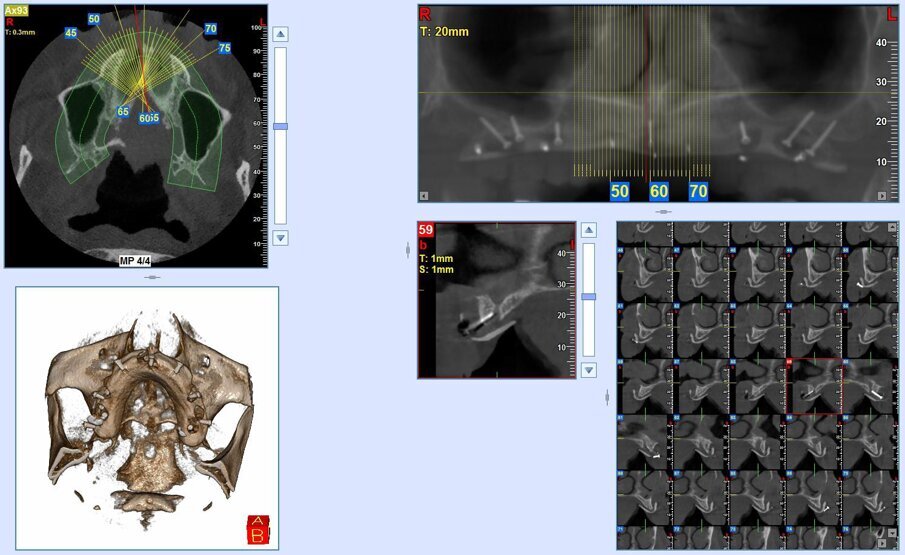

Inoltre l’aiuto della chirurgia navigata, consente di posizionare gli impianti in una posizione pianificata in precedenza ben distribuita lungo l’arcata, limitando al massimo i disparallelismi e semplificando le fasi protesiche.

Gli impianti vengono distribuiti lungo tutta l’arcata cercando il parallelismo e limitando il più possibile i cantilever (6-7 impianti superiori e 5-6 impianti inferiori). La scelta di utilizzare i monconi dritti (grazie al parallelismo degli impianti) è da preferire in quanto quest’ultimi sono anche i più robusti e resistenti nel tempo al carico assiale; inoltre caricano l’impianto lungo il suo asse limitando i carichi disassati. Una volta elevato il lembo mucoperiosteo ed evidenziato l’osso alveolare o basale, attenzione deve essere fatta nel fare un’ostectomia riduttiva mediante una fresa a palla del diametro di 0,6-0,8 cm per creare un piano più uniforme possibile tale da formare una piattaforma d’osso alla stessa altezza, guadagnando anche spessore V-L ed uniformità. Gli impianti devono essere posizionati alla stessa altezza tra di loro e distanziati in maniera tale da favorire le manovre di igiene orale inter-implantare. Una volta posizionate le fixture sottocrestali (1-3 mm) come descritto, vanno connessi i monconi solitamente con collare mucoso di 3-4,5 mm in altezza, ponendo particolare attenzione che i tessuti molli suturati non coprano la parte di accoppiamento conometrico. Verificato il parallelismo corretto dei monconi mediante i pin parallelizzatori, siamo certi che l’accoppiamento e la disconnessione delle cappette contenute nella protesi potrà avvenire nel miglior modo possibile senza creare tensioni.